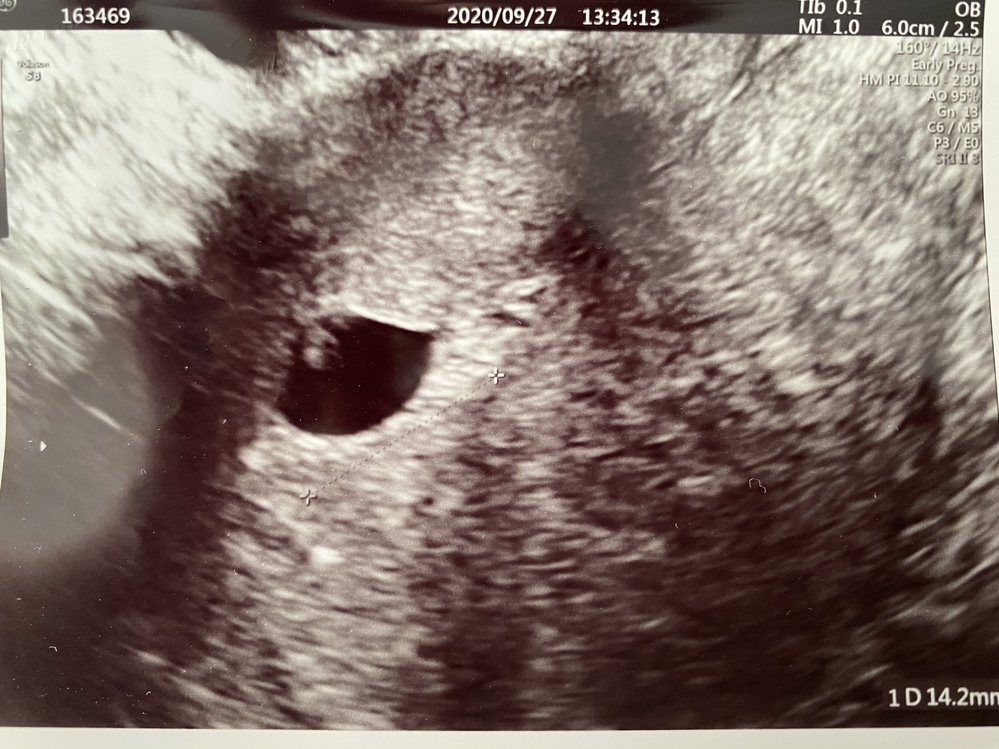

体外受精で7週4日 7w4d 胎嚢14 2センチ胎芽推定2ミリでした Yahoo 知恵袋